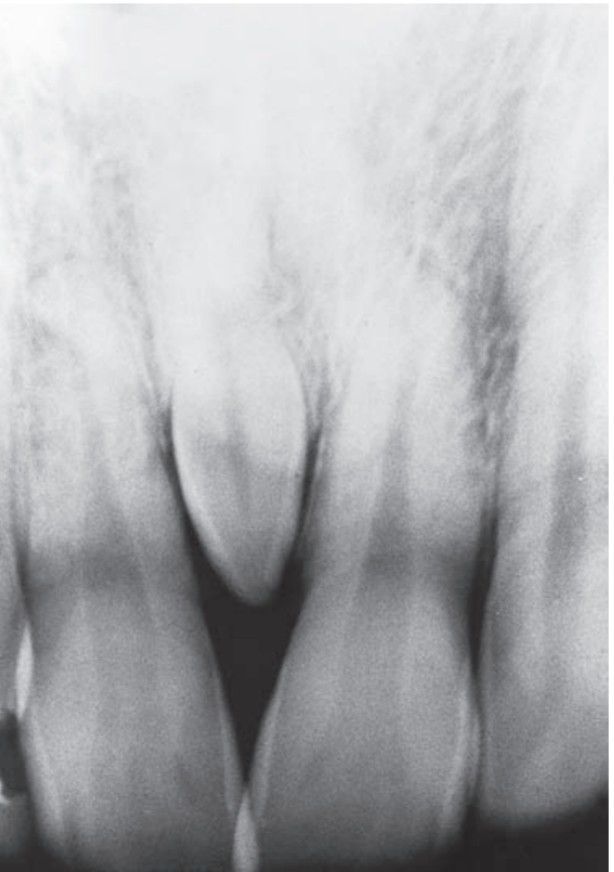

Mesiodens

Extra, or supernumerary, teeth in the dentition most probably result from continued proliferation of the permanent or primary dental lamina to form a third tooth germ